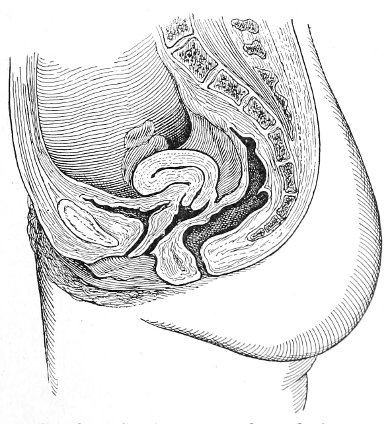

The examination of the uterus and other pelvic structures is often facilitated by dragging the uterus downward with a tenaculum while the vaginal or the bimanual examination is being made. Sensation in the cervix is so slight that little or no pain is experienced in this procedure. The anterior or posterior lip of the cervix is caught with the single or the double tenaculum (Fig. 4), guided along the vaginal finger or introduced through the speculum, and the uterus is drawn down by an assistant in case the bimanual examination is being made, or by the external hand of the examiner in case a simple vaginal examination is made. When this is done the utero-sacral ligaments are made tense, and can be felt like two cords extending from the sides of the cervix outward and backward to the pelvic wall. The posterior surface of the uterus can be palpated often as high up as the fundus. The method is especially useful when the examination is made by the rectum, and in this way the whole posterior surface and the fundus of the uterus may be palpated (Fig. 5).

Fig. 5.—Bimanual examination with one finger in the rectum. The uterus is drawn down with the double tenaculum.

Rectal examination of the pelvic structures is made in a way similar to that already described for the vaginal examination. Bimanual examination may be made by palpating the various organs between the rectal finger and the abdominal hand.